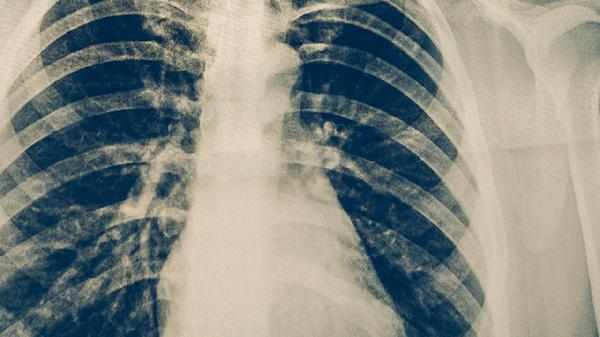

肺結(jié)核的化學(xué)治療需遵循早期、聯(lián)合、適量、規(guī)律、全程原則,主要采用異煙肼片、利福平膠囊、吡嗪酰胺片、乙胺丁醇片、鏈霉素注射液等抗結(jié)核藥物組合方案。治愈需持續(xù)用藥6-9個月,具體方案由醫(yī)生根據(jù)病情調(diào)整。

肺結(jié)核化學(xué)治療的核心是聯(lián)合用藥,通過多種藥物協(xié)同作用殺滅結(jié)核分枝桿菌。異煙肼片能抑制細(xì)菌細(xì)胞壁合成,利福平膠囊可阻斷RNA轉(zhuǎn)錄,吡嗪酰胺片在酸性環(huán)境中殺菌效果顯著,乙胺丁醇片干擾細(xì)菌RNA合成,鏈霉素注射液則通過抑制蛋白質(zhì)合成發(fā)揮作用。治療分為強化期和鞏固期,強化期通常2個月使用四種藥物快速殺菌,鞏固期減少至兩種藥物防止復(fù)發(fā)。治療過程中需定期監(jiān)測肝功能、視力等指標(biāo),因利福平可能引起肝損傷,乙胺丁醇可能導(dǎo)致視神經(jīng)炎。耐藥結(jié)核病需采用二線藥物如左氧氟沙星片、阿米卡星注射液等,療程延長至18-24個月?;颊卟豢勺孕型K?,否則易產(chǎn)生耐藥性。